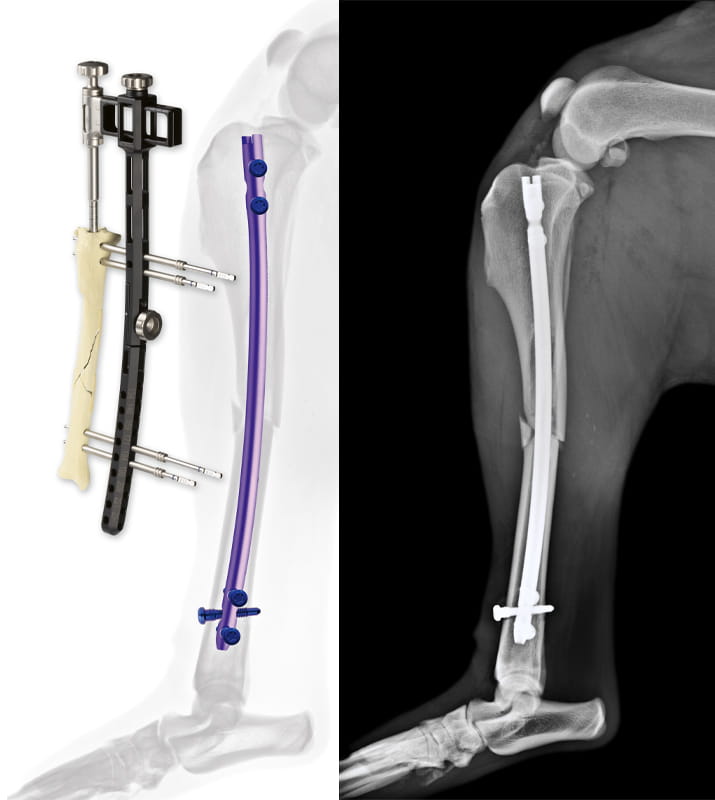

Surg’X offers the first angle-stable, anatomical, titanium interlocking nail for the treatment of long bone fractures in small animals.

Surg’X’s system incorporates technical features hitherto reserved for human surgery:

- Anatomical curved nail

- Titanium alloy implants

- Advanced multi-planar locking system

- Cannulated nail

Nails: ø 3.5 / 4.0 / 5.0 / 6.0 / 8.0mm, length 70-234mm

Screws: ø 2.0 / 2.5 3.0 / 3.5, length 10-48mm